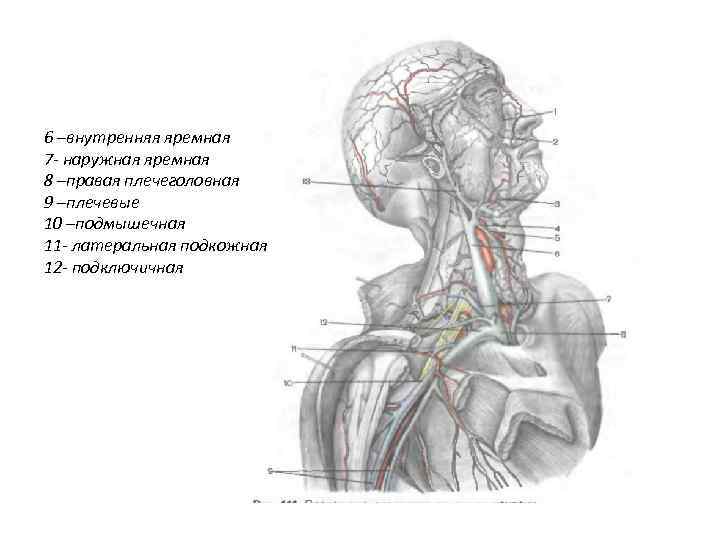

Анатомия внутренней яремной вены: КТ изображения